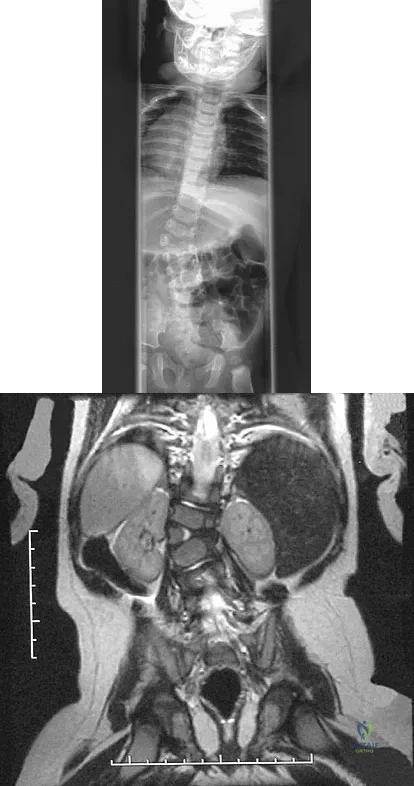

Figures 31a and 31b show the radiograph and MRI scan of an otherwise normal 3-month-old infant who has a spinal deformity. MRI reveals no intraspinal anomalies. What is the next step in management?